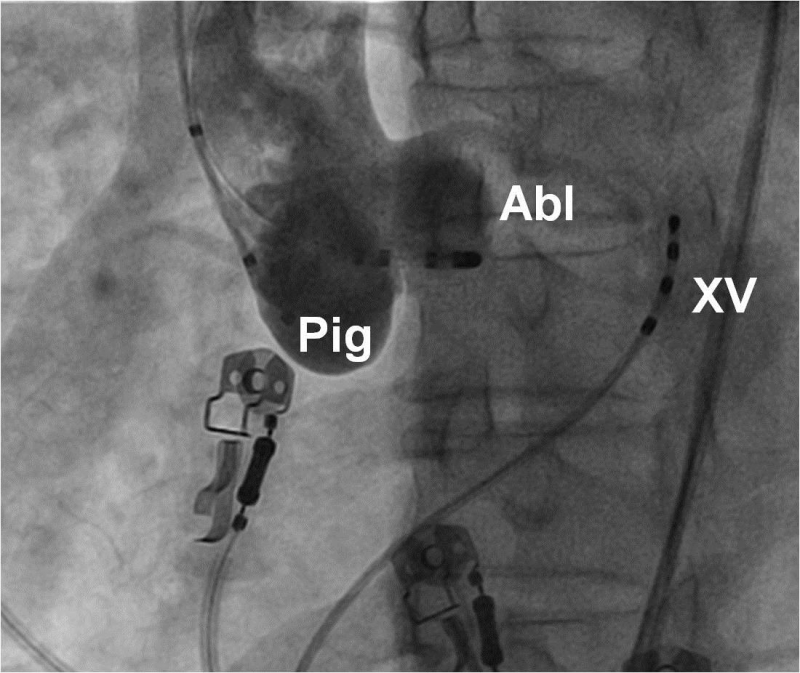

Hình 7: Vị trí các ống thông trên hình ảnh X quang trong triệt đốt đường dẫn truyền phụ: NP: điện cực cùng cao nhĩ phải, His: điện cực vị trí bó His, XV: điện cực xoang vành, TP: điện cực mỏm thất phải, Abl: điện cực triệt đốt được đưa vào thất trái ngược chiều qua van động mạch chủ và cắm vào vòng van hai lá nơi có đường dẫn truyền phụ nhĩ-thất đi qua.

Hình 14: Vị trí các ống thông trên hình ảnh X quang trong triệt đốt ngoại tâm thu thất khởi phát từ đường ra thất phải trên góc nghiêng phải 30 độ: Pig: ống thông Pigtail chụp buồng thất phải, Abl: điện cực triệt đốt được đưa vào vùng đường ra thất phải, ngay dưới van động mạch phổi

Hình 16: Vị trí các ống thông trên hình ảnh X quang trong triệt đốt ngoại tâm thu thất khởi phát từ xoang Valsalva trên góc nghiêng trái 30 độ: XV: điện cực xoang vành, Pig: ống thông Pigtail chụp xoang Valsalva, Abl: điện cực triệt đốt được đưa vào trong lòng xoang Valsalva lá vành trái, phía trên khoảng 1 cm là lỗ xuất phát của thân chung động mạch vành trái.